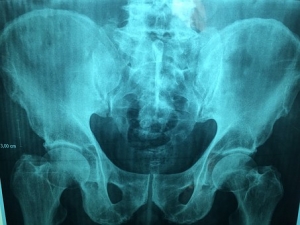

Imagiologia na Osteopatia

A imagiologia como complemento da anamnese em medicina osteopática é uma mais valia. O Osteopata tem uma avaliação adaptada á sua própria filosofia, em muitos aspetos considerados irrelevantes noutras áreas da saúde, são completamente válidos na leitura osteopática. Pormenores no Raio X por exemplo, como assimetrias dos ilíacos, rotações e inclinações vertebrais, calcificações, etc. , podem evidenciar anomalias fundamentais na avaliação clínica final e posteriormente na sugestão e desenvolvimento de um tratamento mais eficaz. Contudo o Osteopata tem métodos próprios de anamnese que solidificam ou complementam os achados clínicos nestes exames.